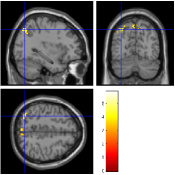

Concerning the Lc-Rc contrast on the data acquired with , Fig. 7 [top] shows that all reconstruction methods enable to retrieve the expected activation in the right precentral gyrus. However, when looking more carefully at the statistical results (see Tab. 2), our pipeline and especially the 4D-UWR-SENSE algorithm retrieves an additional cluster in the right middle frontal gyrus. On data acquired with , the same Lc-Rc contrast elicits similar activations, i.e. in the same region. As demonstrated in Fig. 7 [bottom], this activity is enhanced when pMRI reconstruction is performed with our pipeline. Quantitative results in Tab. 2 confirm numerically what can be observed in Fig. 7: larger clusters with higher local -scores are detected using the 4D-UWR-SENSE algorithm, both for and . Also, a larger number of clusters is retrieved for using wavelet-based regularization.

In order to investigate the smoothing effect introduced by our algorithm, spatial smoothing in the pre-processing pipeline has been turned off and statistical results are illustrated in Fig. 7 [right] and Tab. 2 (Unsmoothed 4D-UWR-SENSE). As expected, qualitative and quantitative results show that deactivating the spatial smoothing gives slightly higher -score values for activation maxima. However, smaller activated clusters are detected compared to results obtained based on smoothed data. As regards the temporal regularization effect, statistical results (not shown here) obtained with 3D-UWR-SENSE reconstructed images show intermediate performance which lies between those of the 2D (UWR-SENSE) and 4D (4D-UWR-SENSE) versions. Indeed, such a regularization helps improving the BOLD signal contrast which allows us to retrieve higher activation peaks.

| mSENSE | UWR-SENSE | 4D-UWR-SENSE | Unsmoothed 4D-UWR-SENSE | |

|---|---|---|---|---|

|

|

|

|

|

|

|

|

|

| cluster-level | voxel-level | |||||

| p-value | Size | p-value | T-score | Position | ||

| mSENSE | 79 | 6.49 | 38 -26 66 | |||

| UWR-SENSE | 144 | 0.004 | 5.82 | 40 -22 63 | ||

| 21 | 0.064 | 4.19 | 24 -8 63 | |||

| 4D-UWR-SENSE | 189 | 0.001 | 7.03 | 34 -24 69 | ||

| 53 | 0.001 | 4.98 | 50 -18 42 | |||

| 47 | 0.001 | 5.14 | 32 -6 66 | |||

| Unsmoothed 4D-UWR-SENSE | 112 | 0.001 | 7.26 | 34 -24 69 | ||

| 21 | 0.001 | 4.77 | 32 -6 66 | |||

| 19 | 0.001 | 4.98 | 50 -18 42 | |||

| mSENSE | 0.006 | 21 | 0.295 | 4.82 | 34 -28 63 | |

| UWR-SENSE | 33 | 0.120 | 5.06 | 40 -24 66 | ||

| 4D-UWR-SENSE | 51 | 0.006 | 5.57 | 40 -24 66 | ||

| Unsmoothed 4D-UWR-SENSE | 25 | 0.001 | 5.7 | 40 -24 66 | ||